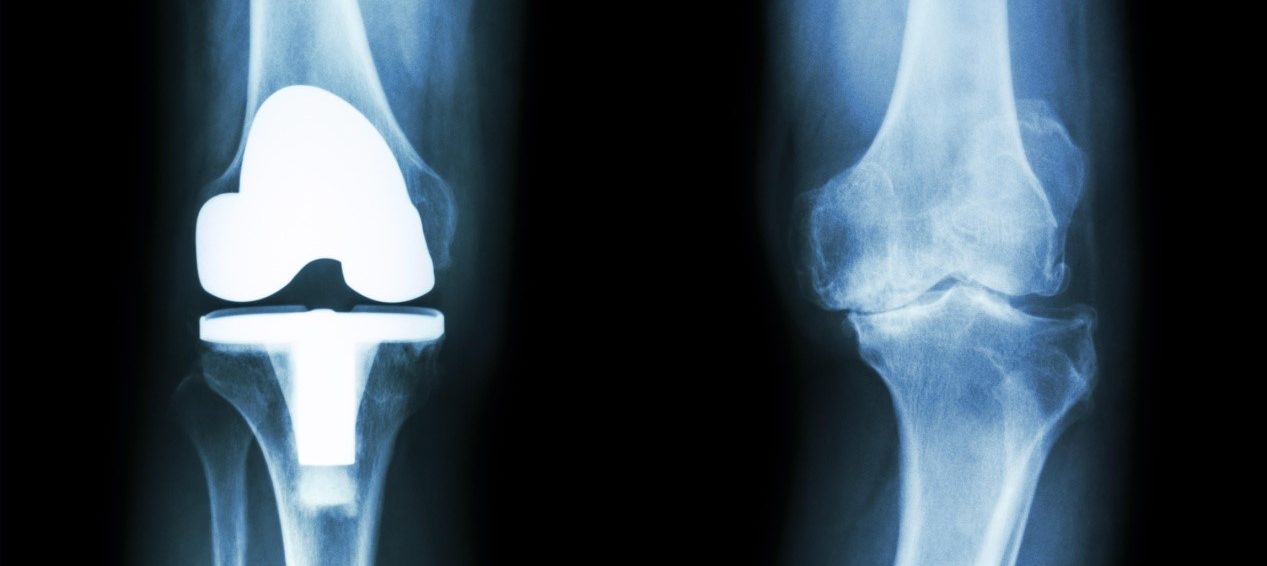

作为关节炎最先进的治疗方法之一,每年进行的全关节置换手术(TJR)超过100万例。长期研究表明,近20%的患者会逐渐发生假体周围骨溶解和骨丢失,这意味着翻修手术是不可避免的。如果不及时治疗,假体周围骨溶解将最终导致关节松动甚至骨质流失。整个病理过程与种植体产生的磨损颗粒密切相关。这些磨损颗粒可以被周围的巨噬细胞吞噬。在摄入小磨损颗粒后,这些髓系免疫细胞将被刺激分泌炎症细胞因子,包括白细胞介素1β (IL-1β),白细胞介素6 (IL-6),前列腺素E2 (PGE2)和肿瘤坏死因子(TNF)。这些细胞因子,特别是IL-1β,与破骨细胞活化和骨吸收有关。